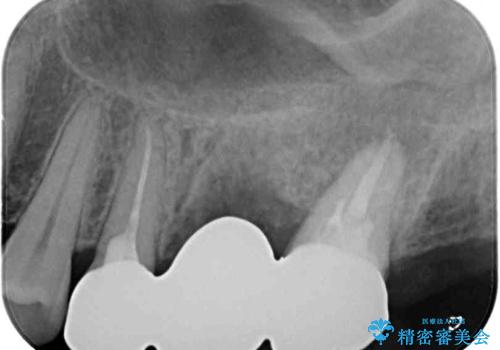

歯根の先端に病変の認められた奥歯は、補綴前に根管治療を行うこととしました。

違和感を感じていた歯は虫歯が非常に大きく、骨に到達するほどの穴が空いていました。